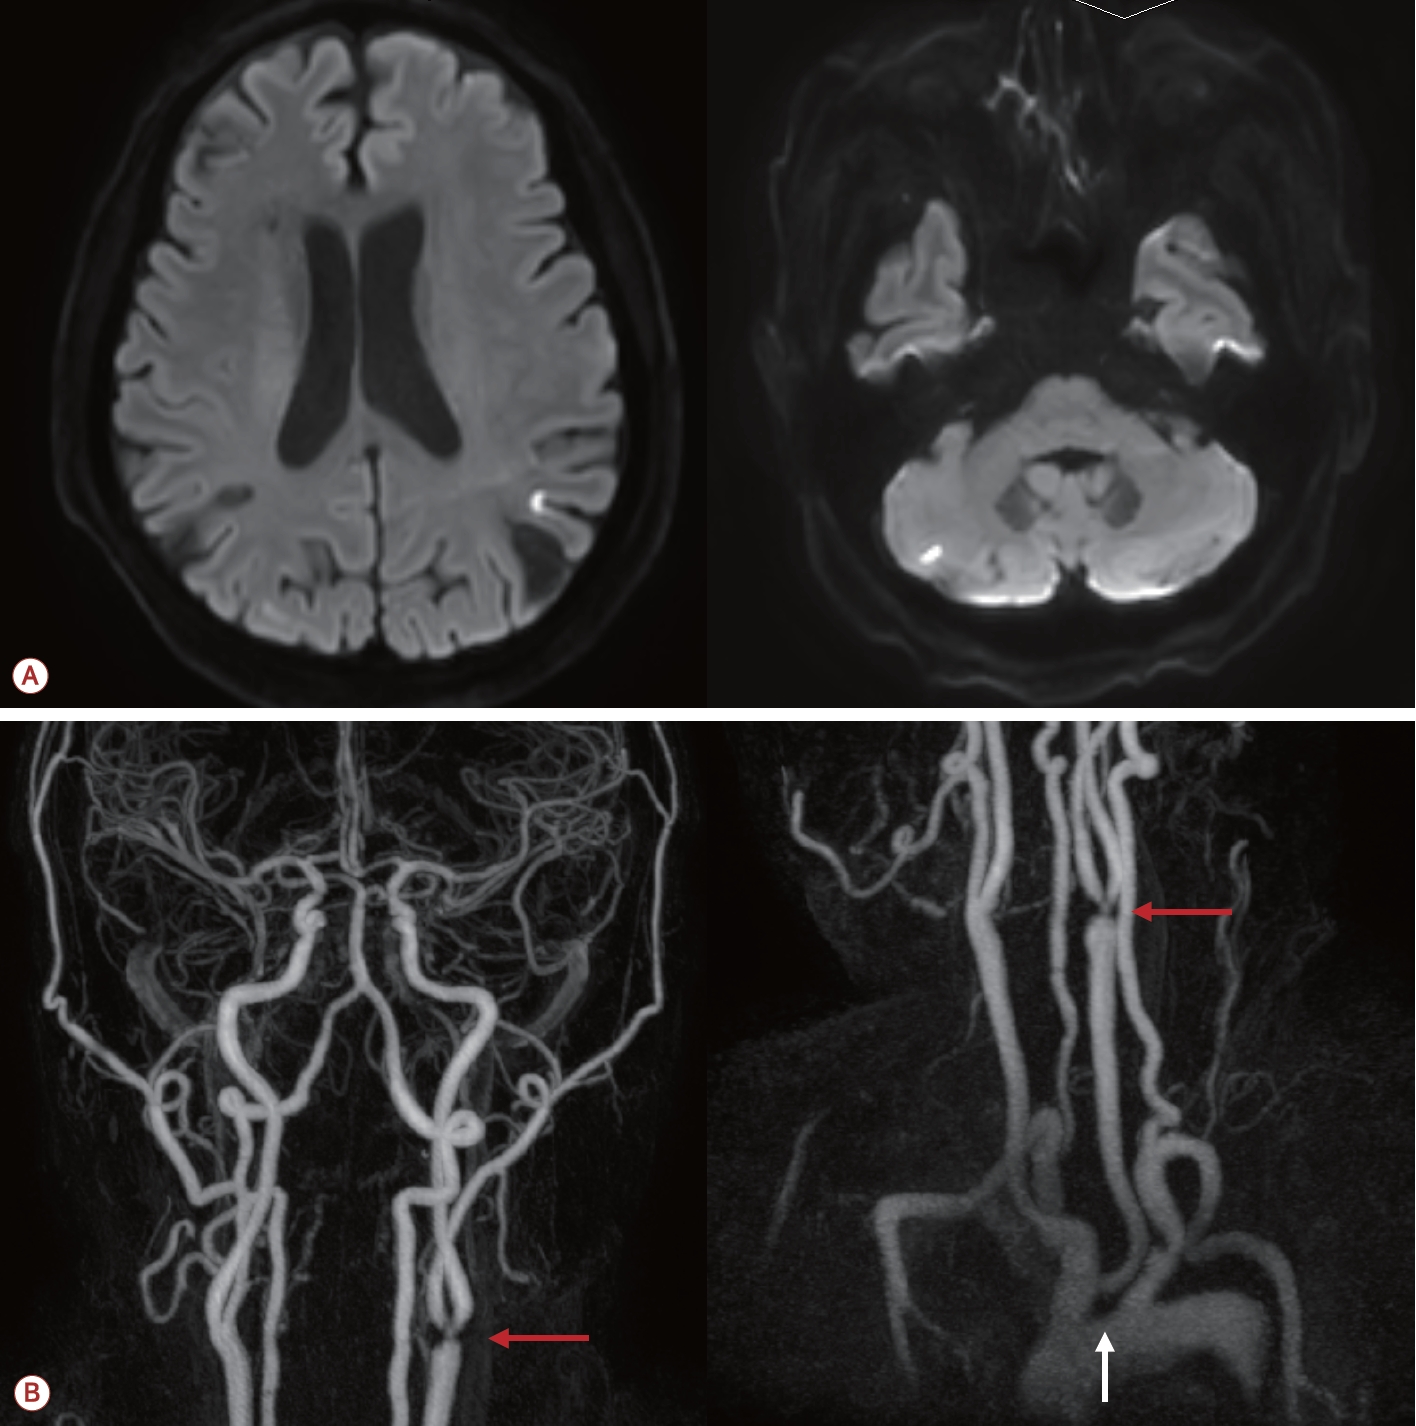

73세 남자가 최근 3개월간 반복적인 허혈뇌졸중으로 내원하였다. 환자는 고혈압, 당뇨, 안정협심증의 기저 질환을 가지고 있었다. 초기 뇌자기공명영상(magnetic resonance [MR] imaging)에서 좌측 대뇌반구와 우측 소뇌에 다발성 허혈 병변이 관찰되었으며(Fig. 1-A) 혈관 검사에서는 좌측 내경동맥근위부(internal carotid artery, ICA)에 76.7%의 협착(NASCET 기준)이 확인되었고 동시에 보바인형 대동맥궁(bovine arch, 공통 기시형 변이)이 관찰되었다(Fig. 1-B). 이에 따라 증상성 중증도 이상의 ICA 협착으로 판단하여 좌측 CEA와 이중 항혈소판 요법이 시행되었다. 그러나 시술 2개월 후에 우측 후 대뇌동맥(posterior cerebral artery, PCA)과 우측 중대뇌동맥(middle cerebral artery, MCA) 영역에 재발성 뇌경색이 발생하였고(Fig. 2-A) 한 달 후에는 좌측 MCA와 PCA 영역에 새로운 뇌경색이 재발하였다(Fig. 2-B). 기존에 진행되었던 두개경유도플러 검사에서 심방중격 결손이나 미세색전 신호를 시사하는 소견은 확인되지 않았고 흉부경유심초음파에서 좌심실 박출률은 정상 범위었으며 3일의 홀터 모니터링에서도 심방세동은 관찰되지 않아 심장성 색전은 배제하였다. 반복되는 색전성 병변의 원인을 찾기 위하여 식도유심초음파(transesophageal echocardiography, TEE)가 진행되었으며 대동맥궁 대만부(greater curvature)에 위치한 7 mm 크기의 궤양성(ulcerated), 유동성(mobile)의 고위험 죽경화판(high-risk aortic arch plaque)이 관찰되었다(Fig. 2-C). 추가적인 머리 혈관조영에서는 기존에 확인되었던 좌측 경동맥의 중증도 협착은 호전 상태를 보였으며 보바인형 대동맥궁 및 팔머리동맥에 동맥류성 확장(aneurysmal dilatation)을 확인할 수 있었다(Fig. 3-A). 이에 신경과, 순환기내과, 영상의학과, 심장혈관흉부외과가 포함된 다학제 협의를 통해 단계적 하이브리드 치료가 결정되었다. 첫 번째 단계로 부분 디브랜칭 수술(좌쇄골하-좌총경동맥우회술[partial debranching surgery, left subclavian-left common carotid artery bypass])이 시행되었다. 수술 한 달 후에 팔머리동맥에 스텐트이식편(endovascular brachiocephalic stent-graft)을 삽입하여 팔머리동맥류의 병적 분절을 제거하였다(Fig. 3-B, C). 스텐트 시술 이후 약 1년 6개월이 지난 현재까지도 환자는 지속적으로 이중항혈소판 요법을 유지하면서 추가적인 허혈 사건 없이 안정적으로 추적 관찰 중이다.